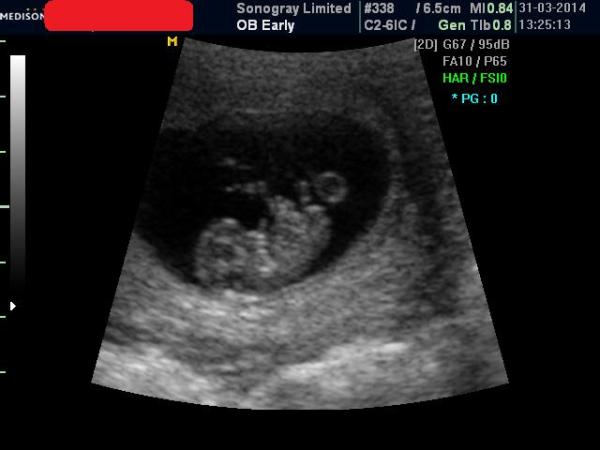

Regardless here is my little gummy bear. 9+2. Smile

November 2014 Thread 2: Springing through the first trimester!

Random try not to worry. I imagine it was more that she was conscious that your scan was at the 'later' end of the 10-13 week timeframe and if you did want to partake in screening you might miss out if it were any later. I imagine that was why she said it rather than as a result of her having seen anything concerning. Cute picture too!

Aw random that's amazing- such a big development change from when I had mine at 6 +5- in just 3 weeks it looks so much like a baby :P